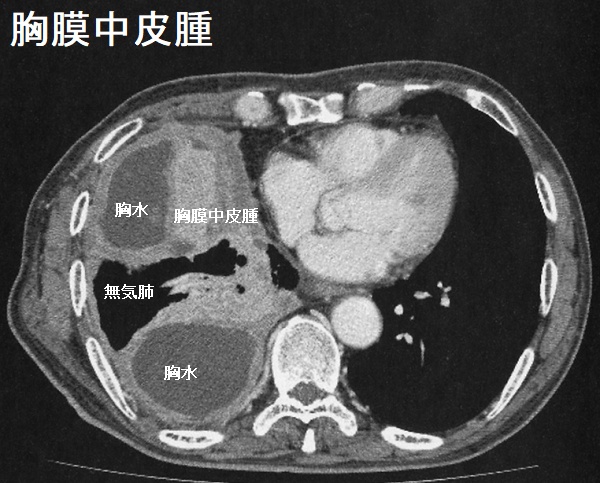

胸膜中皮腫

悪性中皮腫の甲状腺転移

悪性中皮腫のⅣ期には脳、脊柱、甲状腺に遠隔転移します。筆者の経験では、悪性中皮腫の甲状腺転移は、原発巣と同じような粗大な(巨大な)石灰化が見られます。[Pathol Res Pract. 1995 Jun;191(5):456-60; discussion 461-2.]

他の報告では、下記の様に石灰化を伴わない事もあります(Cytojournal. 2014 May 22; 11: 11.)

悪性中皮腫の甲状腺転移では、他臓器にも多発性転移を認めます(Pathol Res Pract. 1995 Jun;191(5):456-60; discussion 461-2.)。